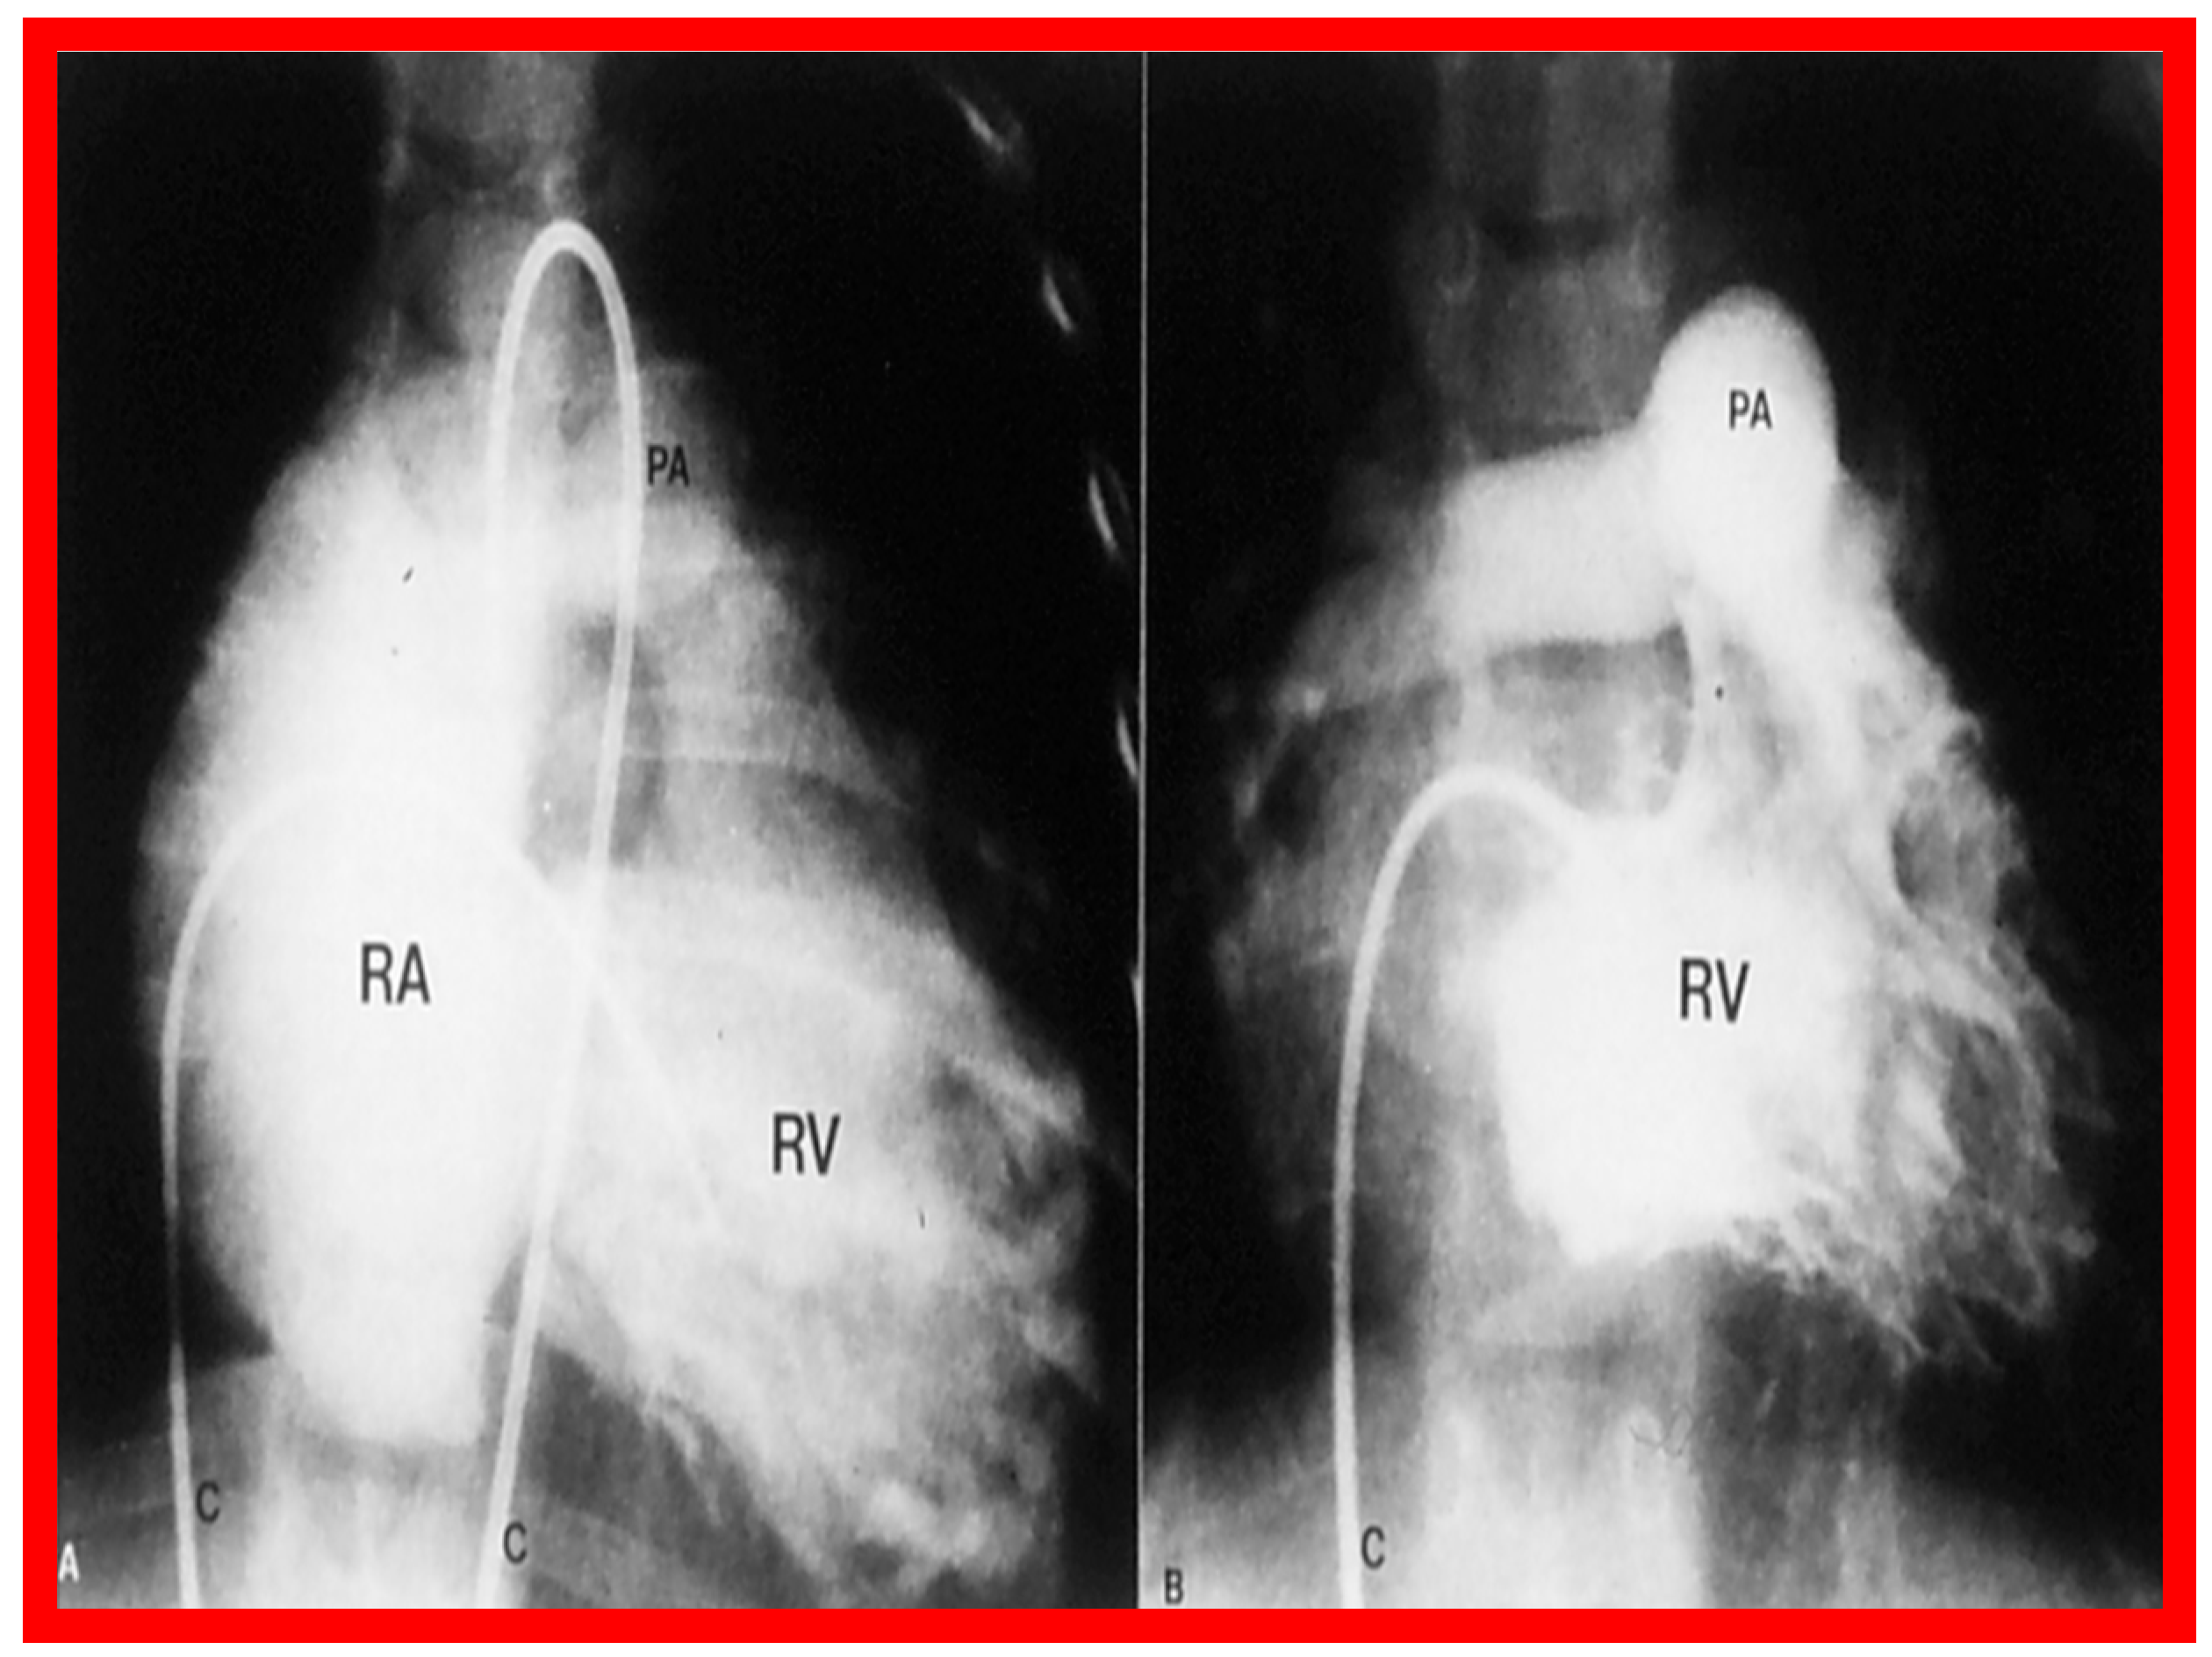

3.1. Pulmonary Stenosis

4.1. Pulmonary Stenosis